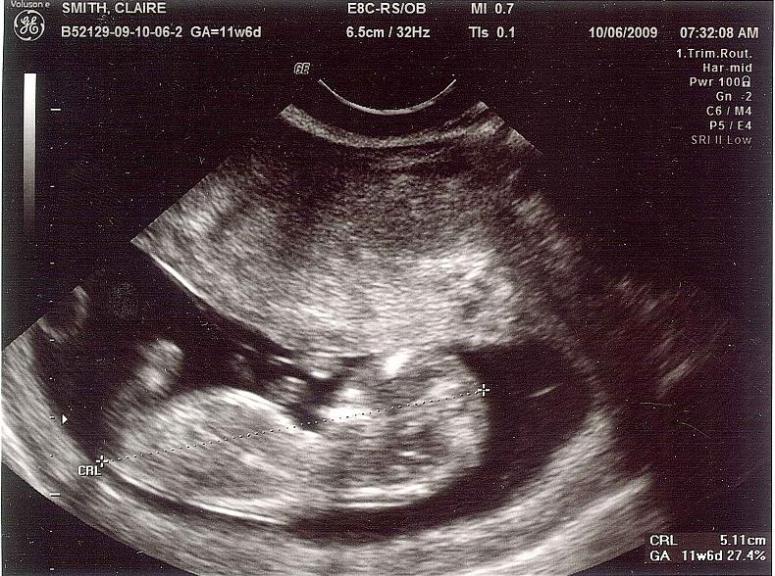

It’s true. I have proof:

There it is: the kidlet at 12 weeks. It looks so… huge to me. I guess when Elliot had his first picture taken, he was only 10 weeks. It makes a big difference apparently. The bean is growing right on schedule and my supposed due date is right about 4/21, which will make it the end of the semester, thankfully. However, I have a habit of producing children that like to show up early. Let’s hope for one that’s on time, ok?